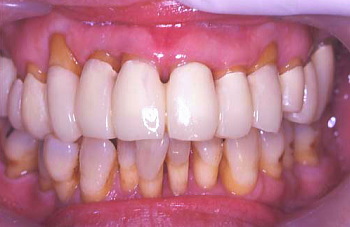

① 初診時の口腔内の状態:歯と歯の間に黒い歯石が見られ、歯肉は腫れている。

初診時の口腔内の状態